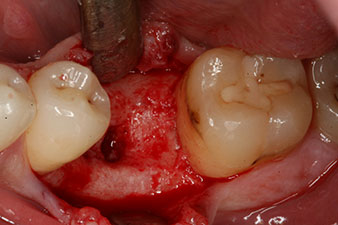

Cependant, six semaines après l’extraction on observe une ossification incomplète après la préparation du lambeau mucopériosté dans la région de l’ancienne alvéole mésiale.

L’implant a été posé comme prévu après élimination complète du tissu de granulation (blueSky, bredent).